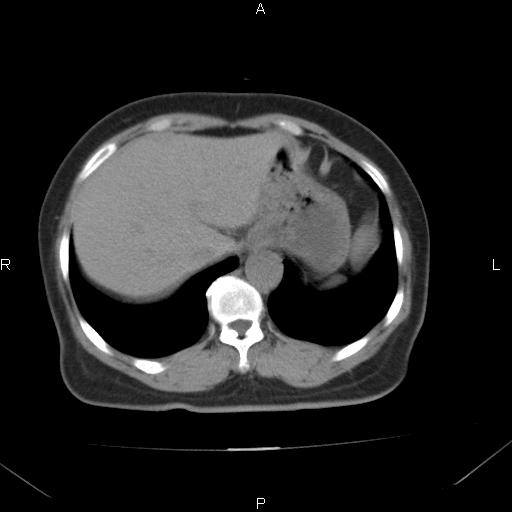

胸腺瘤

女、63Y 双眼睑下垂,早轻晚重。 胸腺瘤???

结果胸腺瘤